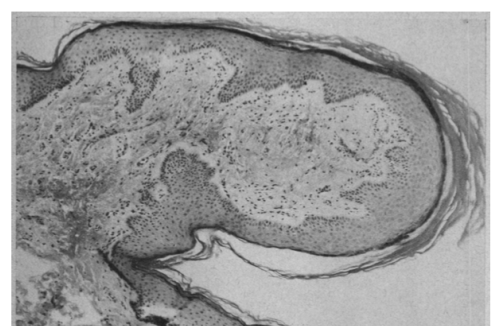

The accompanying figure compares histological sections through the penile spines of mice and chimps, and a penile papule in humans.

In contrast, a PPP in humans consists of a larger out-pocketing of the entire skin, without local layering of the keratinized epidermis to make hook-like projections, and with the bulk of the overall structure consisting of a dense, well vascularized core of connective tissue cells, rather than epithelial cells (bottom row).

The different structure of a human penile papule

Unlike the keratinized spines shown above, the papules that form in some humans are outpockets of the entire skin surface, with a dense and vascularized connective tissue core making up the bulk of the projection. Although mouse and chimp penile spines are closely associated with neural sensory receptors, human PPP are not enriched in neural structures (see Glicksman and Freeman (1966) Arch Derm 93: 56-59).